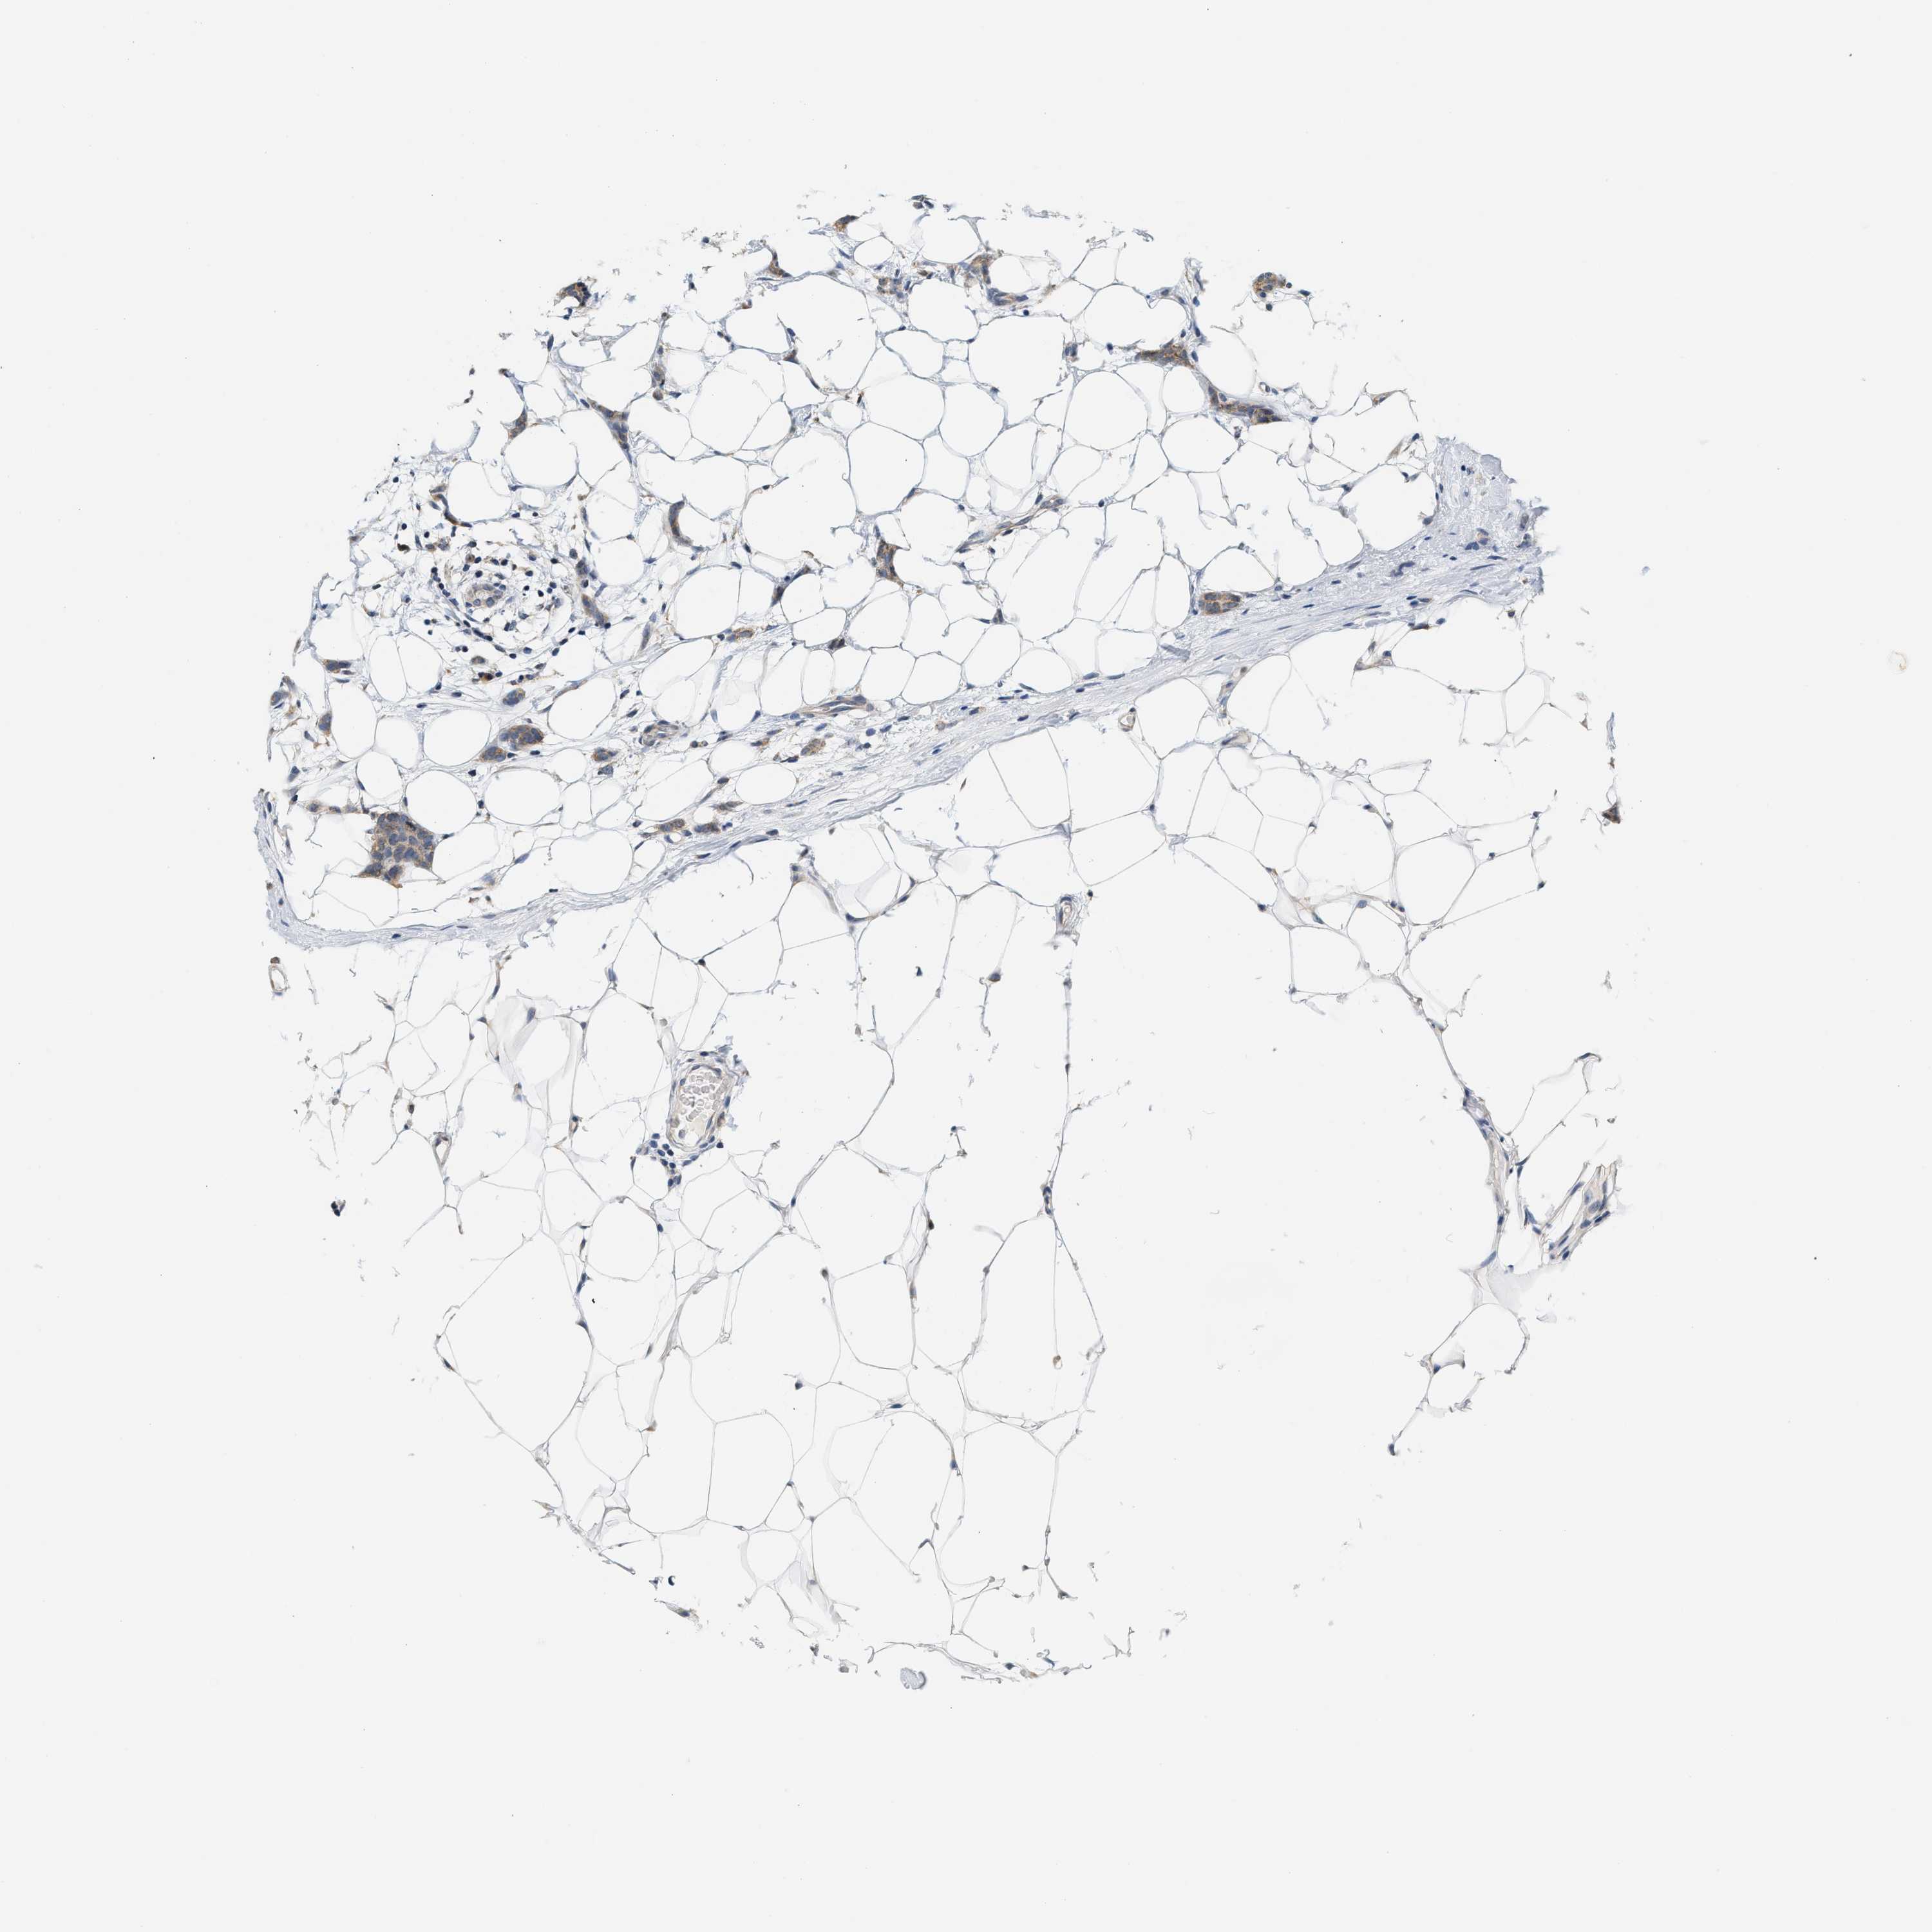

CANCER BREAST CANCER Show tissue menu

BRCA TCGA BRCA VALIDATION PROTEIN EXPRESSION